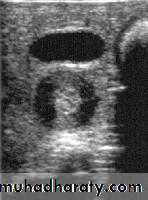

Pyloric stenosis is relatively common and has a male predilection (M:F ~ 4:1), and is more commonly seen in Caucasians 4. It typically occurs between the 4-8 weeks of life. There may be a positive family history. Incidence of hypertrophic pyloric stenosis is approximately 2-5 per 1,000 births per year in most white populations,Hypertrophic pyloric stenosis refers to idiopathic thickening of gastric pyloric musculature which then results in progressive gastric outlet obstruction

In a normal situation, the pyloric muscle thickness (diameter of a single muscular wall on a transverse image) should normally be less than 3 mm (most accurate 3) and the length (longitudinal measurement) should not exceed 15 mm.